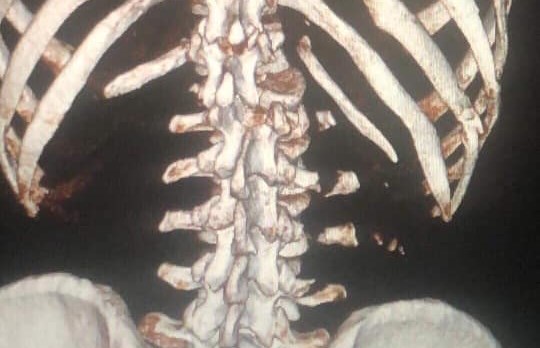

В резултат на това, Йоско получи множество тежки травми – разкъсвания на бял и черен дроб, черепно-мозъчна травма и счупване на гръбначния стълб.

В момента Йоско е в УМБАЛ "Канев" - Русе, обездвижен и под медикаментозно лечение. На 25 юли ще бъде транспортиран в болница Токуда в София, където ще му бъде направена спешна операция.